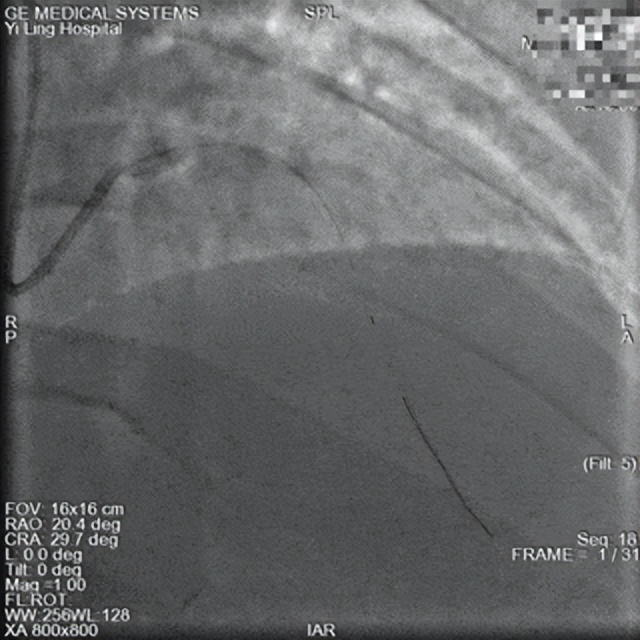

术后

15时57分,患者进入导管室。急诊冠脉造影显示前降支严重狭窄伴血栓影,需紧急介入治疗。在获得家属知情同意后,心血管病科一病区葛岳鑫副主任迅速为患者前降支置入支架1枚,成功解除狭窄病变。手术于16时17分顺利完成,全程仅用时20分钟。

术后,在杨胜利院长的指导下,科室团队采用中西医结合治疗方案。以络病理论为指导,结合患者具体情况辨证施治,最终成功阻断心肌梗死演变进程。复查心电图及心肌酶谱均显示治疗效果显著,有效预防了患者心肌梗死相关并发症的发生。